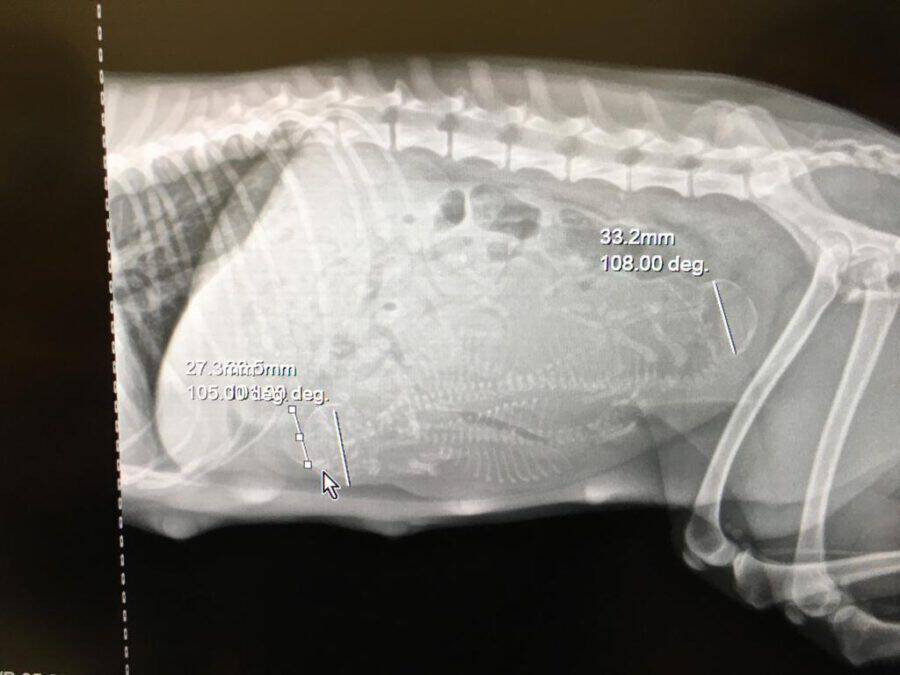

Nach kurzer Zeit hat sich herausgestellt, dass Ginny trächtig ist. Am 30.08.21 haben 3 wunderbare, kleine Welpen das Licht der Welt erblickt und werden von ihrer Mama toll umsorgt.